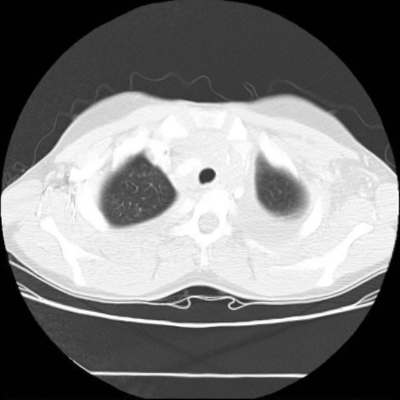

We now consider applying the proposed image registration method on real lung CT images retrieved from the National Lung Screening Trial (NLST) dataset [1]. Fig. 9(a) and Fig. 9(b) show two slices of lung CT images that we use as the source and the target (see Fig. 9(c) for the absolute intensity difference). We remark that the CT images are originally with different intensity, and so we apply an intensity histogram matching before running the registration experiment. Fig. 9(d) shows the registration result obtained by our proposed method. It can be observed that our method successfully produces a large deformation on the right lung of the source image to match that of the target image (see also Fig. 9(e) for the final absolute intensity difference). On the contrary, DDemons [47] (Fig. 9(f)), LDDMM [5] (Fig. 9(g)), Elastix [29] (Fig. 9(h)) and DROP [18] (Fig. 9(i)) all fail to produce an accurate and bijective registration result. This shows that our method is more capable of handling large deformation image registration.